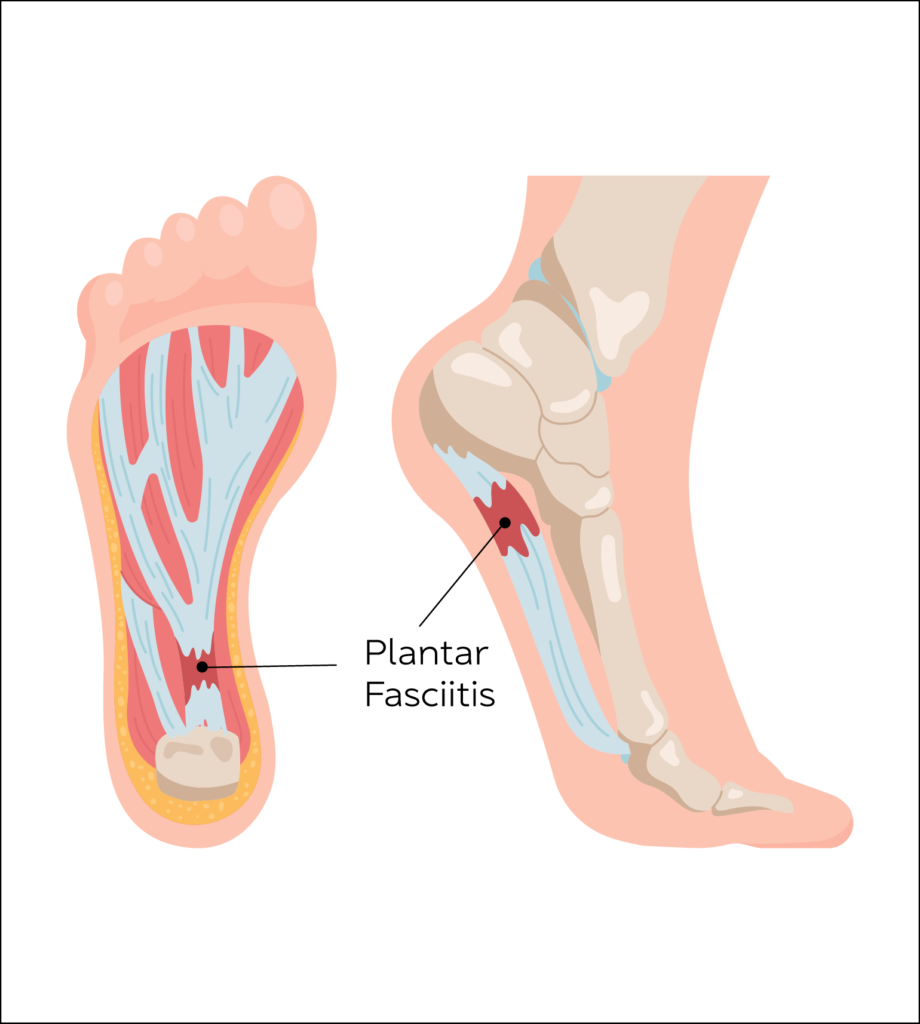

Plantar Fasciitis

Inflammation of a thick band of tissue that runs from the heel to toes at the attachment to the heel.

Affects 3-7% of the population.

The main symptom of plantar fasciitis is morning pain or pain at the beginning of activity after rest, which may worsen by the end of the day.

Ultrasound can be used both as a diagnostic tool and delivering treatment if other modalities of treatment fail to relieve symptoms. Guided injection using steroids relieve inflammation and aid in rehabilitation.